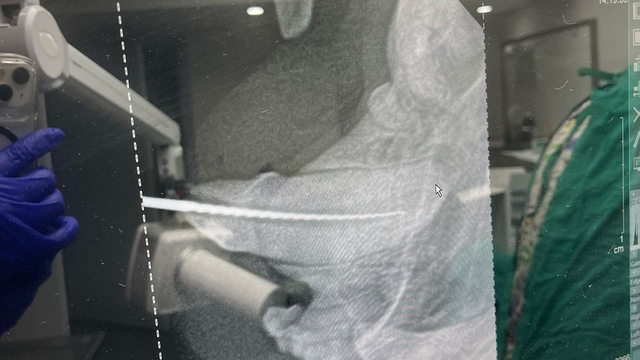

Kediye altın diş yapan ekipte yer alan veteriner hekim Ömer Faruk Alkan, “Genç bir kediydi, British bir çocuktu. Geldiğinde dişinin kırık olduğunu fark ettik. Kedilerin acı eşiği çok yüksektir. Kolay kolay acı hissi olmaz. Ama kırık dişle nasıl insanların canı çok yanıyorsa kedilerin de aynı şekilde canı yanıyor. Biz buradaki muayenede, sinirlerin açık olduğunu gördük. Hasta sahibiyle konuşup önce kanal tedavisi sonra da kaplama tedavisi yapmaya karar verdik. Önce kanal tedavisini yaptık. Altının belli başlı avantajları var metale göre. Hem hafiflik hem de uyum süreci birazcık daha rahat oluyor bizim için” ifadelerini kullandı.

İşlemin yapılmasının üzerinden bir hafta geçtiğini ve kedinin sağlığının iyi olduğunu ifade eden Alkan, “Altınla metal arasında öncelikle ağırlık farkı var. Normal porselen vesaire kediye yapamıyoruz, direnci o kadar yüksek olmuyor. Bir de altının vücuda uyumu daha rahat oluyor. Onun dışında çok büyük bir farkı yok. Maliyet açısından 1,4 gram gibi bir altın gitti, işlemlerin dışında. Altının fiyatı önemli olandı. 5-6 bin lira sadece ham altın gitti” dedi.

“Kökünün belli bir kısmı kalana müdahale edebiliyoruz, kanal tedavisiyle önce sinirleri temizliyoruz. Önce kapatılıyor sonra ya metal ya altın gibi biraz sağlam bir maddeyle dolgu şeklinde bırakılıyor. Tamamı gittiyse ya da tutunacak bir yer yoksa müdahale edilemiyor. Altın diş, internette ve kaynaklarda taradığımız kadarıyla çok fazla yapılmamış. Hatta Türkiye’de herhangi bir kaynak yok, ilk denebilir. Nadir bir uygulama.”